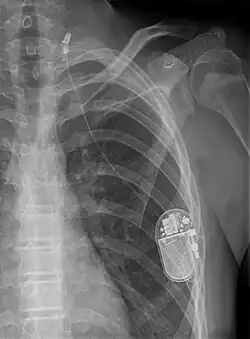

Bei der Vagusnervstimulation (VNS) wird im Brustbereich unter der Haut bei einem minimalinvasiven Eingriff ein Stimulationsgerät ähnlich dem Herzschrittmacher implantiert, das über eine Elektrode meist mit dem linken Nervus vagus verbunden ist. Der Generator sendet regelmäßige elektrische Impulse (meist alle 5 Minuten über 30 Sekunden) über den Vagusnerv an das Gehirn und entfaltet so seine antikonvulsive und antidepressive Wirkung. Die Effektivität und Sicherheit der VNS bei MRE konnte über 20 Jahren in hunderten Studien bestätigt werden. In 13 Klasse III Studien konnte gezeigt werden, dass VNS bei 55 % der Patienten mit medikamentenresistenter Epilepsie eine Anfallsreduktion von 50 % oder mehr erzielt.[2] Bei Langzeitstudien konnte gezeigt werden, dass bei Patienten, die länger als 2 Jahren mit VNS behandelt werden, höhere Anfallsreduktionen bis zu 76 % zu erwarten sind.[3] Neben einer Verringerung der Anfallsfrequenz kann VNS die Anfallsdauer, Anfallsschwere, Dauer der postiktalen Phase[4] und Häufigkeit von Status Epilepticus[5] signifikant reduzieren. Ein Cochrane-Review von vier randomisiert-doppelt-verblindeten Studien zu VNS ergab, dass hochdosierte VNS eine größere Anfallsreduktion als niedrigdosierte VNS verursacht.[6]